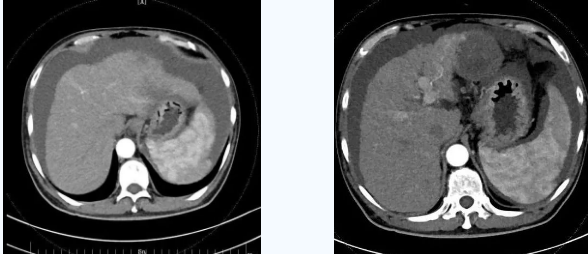

術后一個月秦先生來院復查,腹水已明顯較前減少,精神和飲食較術前明顯好轉。

韓國宏院長介紹,TIPS原理是采用特殊的介入治療器械,在X線透視導引下,經(jīng)頸靜脈入路,建立肝內的位于肝靜脈及門靜脈主要分支之間的人工分流通道,并以金屬覆膜內支架維持其永久性通暢,達到降低門脈高壓后減少腹水產(chǎn)生,控制和預防食道胃底靜脈曲張破裂出血的目的。